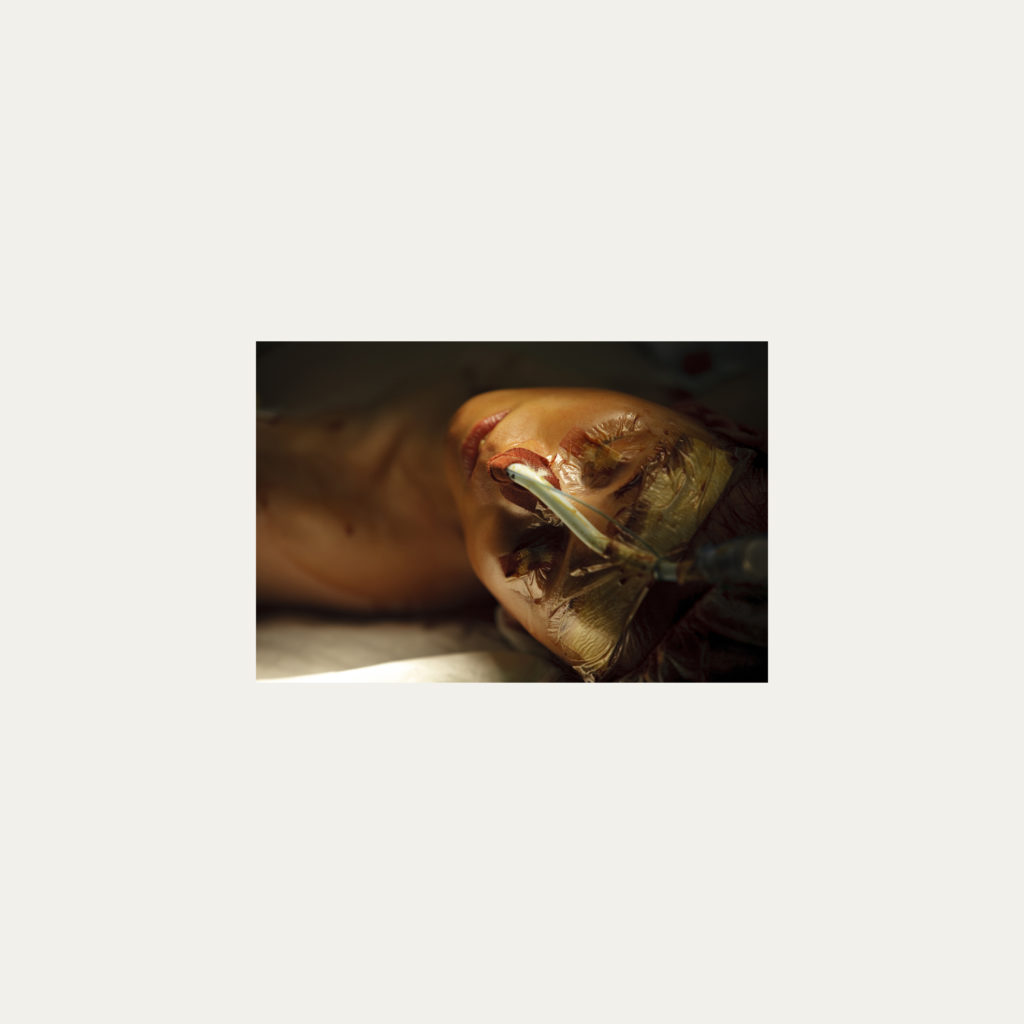

« Nature Morte » est la recherche de l’instant, pendant une intervention chirurgicale où la tête du patient opéré se retrouve seule dans le champ photographié. Aucune main intervenant, peu d’instruments chirurgicaux visibles, laissent le fragment de corps opéré existé pour lui-même. Les têtes, ainsi isolées, en deviennent presque des objets.

Cette approche est intensifiée par la présentation : dans de grands cadres carrés et passe-partout blancs, les photos de petit format font référence aux papillons épinglés de la collection d’un entomologiste.

Face à ces images, une forme de recueillement est nécessaire, s’approcher doucement pour s’approprier tous les détails des images.

Le caractère éminemment esthétique est souligné/donné par les gammes de couleur, la lumière précise sur la tête photographiée, les brillances partielles, renforçant également l’aspect pictural, les textures réelles.

L’humain présent dans ces images est celui qui rompt avec l’invisible et donne à voir l’architecture même de sa chair.